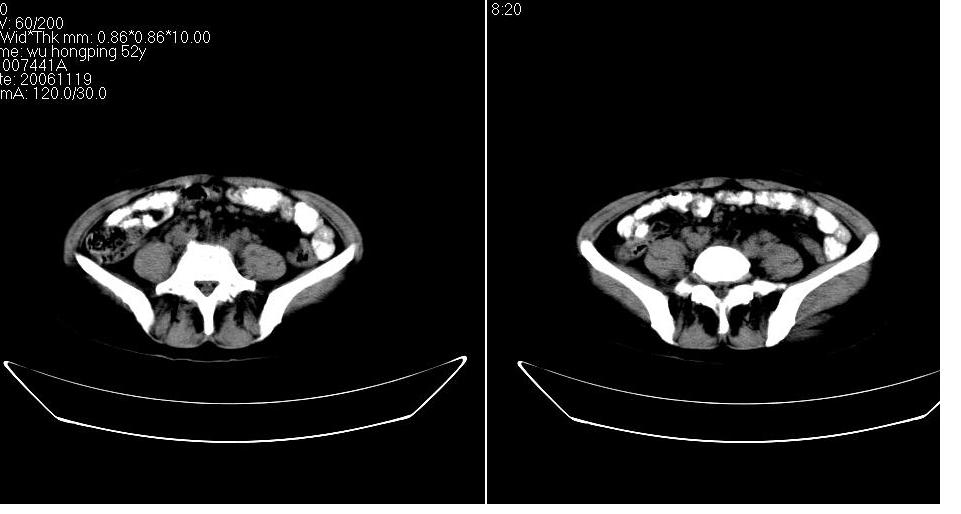

女 53岁,大便每天四到五次,变细,伴有粘液,病人家属说,去年五月在外院行子宫肌瘤术。

腹膜后多发肿大淋巴结肿大并融合改变;右侧回盲部可见团块样软组织影,不规则;

腹膜后诸多淋巴结,右侧髂窝软组织块影,综合患者大便次数、形状改变,考虑结肠回盲部肿瘤

考虑回盲部肿瘤并腹膜后淋巴结转移,建议钡剂灌肠或增强检查。

双侧盆腔均可见不规则形软组织肿块影,似为结节状影融合而成,但以右侧为甚,腹主动脉与下腔静脉周围亦可见多个肿大淋巴结.

结合临床手术史考虑:盆腔与腹膜后多发性淋巴结转移(原发灶可能是原来的\"子宫肌瘤\"恶变或并非\"子宫肌瘤\";回盲部肿瘤不排除)

支持。大便次数多可能系腹膜后肿大淋巴结累及肠腔所致。另外,可钡灌肠检查,进一步观察直肠及其他结肠有否异常。